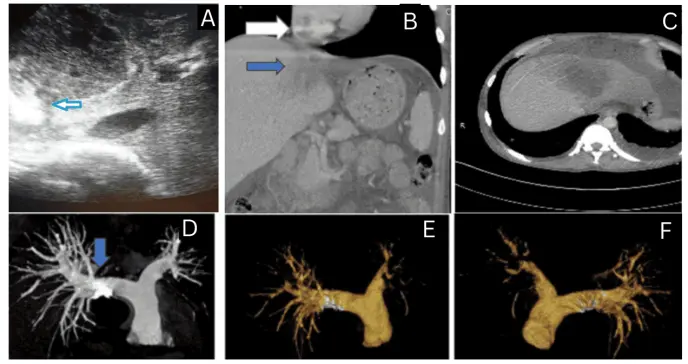

El diagnóstico precoz se apoyó en la sospecha clínica ante síntomas respiratorios y hallazgos electrocardiográficos sugerentes de tensión ventricular derecha, asociado a pruebas de imagen (ecografía, TC contrastada, angio-TC y ecocardiografía) y marcadores de coagulación.

Un caso de ruptura de absceso amébico en la vena cava inferior, con un trombo que se extiende hasta la aurícula derecha y tromboembolismo pulmonar tratado con éxito.

Un hombre indio de 45 años desarrolló una complicación extraordinariamente rara cuando su absceso hepático amébico se rompió directamente en la vena cava inferior, generando un trombo que se extendió hasta la aurícula derecha y provocó tromboembolismo pulmonar bilateral.